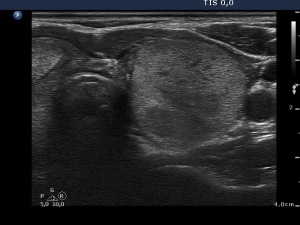

Six months after the therapy (second row of images):

Clinical presentation: the complaints of the patient have disappeared and she did not feel the lesion in the left lobe.

Palpation: the lesion in the left lobe became non-palpable.

Ultrasonography the volume of the treated nodule decreased to less than one-quarter of the original size.

Functional state: euthyroidism with TSH 1.56 mIU/L.